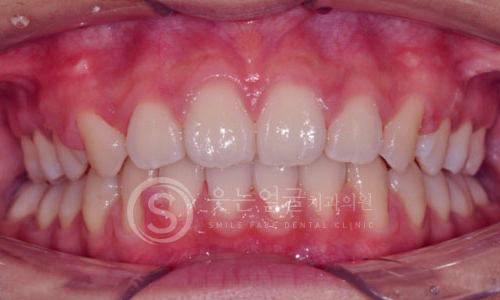

한눈에 보는

임플란트 전후사진

View more